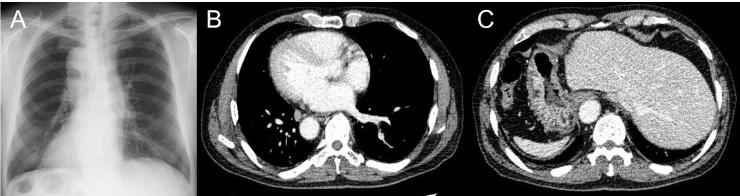

Our first case was of an 82-year-old man who underwent a left thoracoscopic esophagectomy in the prone position, followed by hand-assisted laparoscopic gastric mobilization. Surgical duration and blood loss were 661min and 165g, respectively. His postoperative course was uneventful. The second case was of a 66-year-old man who underwent a left thoracoscopic esophagectomy in the prone position, followed by gastric mobilization via laparotomy owing to a concomitant intestinal malrotation and polysplenia. Surgical duration and blood loss were 637min and 220g, respectively. We trained for the surgical procedures preoperatively using left-inverted and right-inverted thoracoscopic surgical videos of patients with normal anatomy.

全内脏反位(SIT)是一种罕见的先天性疾病,其特征是胸腹部器官完全转位。在此,我们报告两例成功的左侧胸腔镜下食管癌切除术,手术采用俯卧位,适用于全内脏反位相关的食管癌。

我们的首例病例为一名82岁男性,接受了左侧胸腔镜下食管癌切除术,采用俯卧位,随后进行手辅助腹腔镜胃游离术。手术时间和失血量分别为661分钟和165克。他的术后过程顺利。第二例病例为一名66岁男性,接受了左侧胸腔镜下食管癌切除术,采用俯卧位,由于合并肠旋转不良和多脾症,随后通过开腹进行胃游离术。手术时间和失血量分别为637分钟和220克。我们术前使用解剖结构正常患者的左侧和右侧胸腔镜手术视频对手术操作进行了训练。